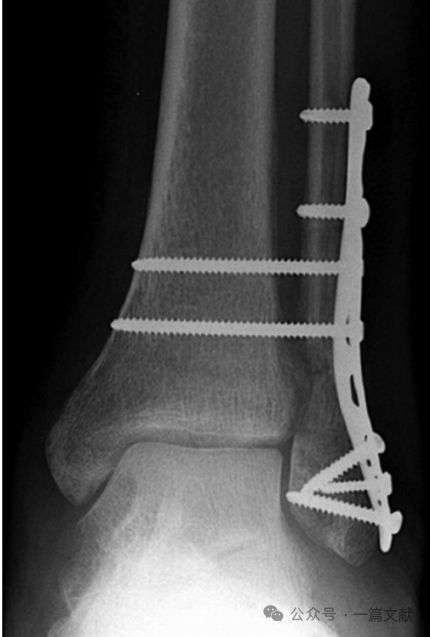

2,中和钢板固定:相对于前述之螺钉固定,钢板固定有以下优点: 1) 此钢板起到类似于螺钉垫圈效果,将螺钉的压力更均匀分布在腓骨表面。2)钢板置于腓骨后外侧,可减少内固定引起的软组织激惹,以及更好的垂直切迹置钉。3)还可避免螺钉过于靠前或靠后拧入造成医源性骨折并最终导致内固定失效。如下图:2枚3.5mm螺钉固定在三孔钢板的两端,行三皮质固定。从左到右依次为前后位,踝穴位,侧位片。

图片